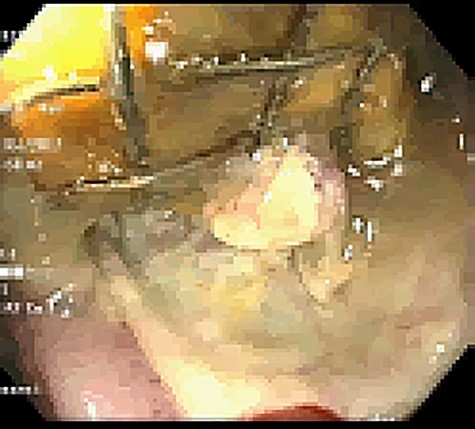

Unfortunately, 6 weeks thereafter he returned with 5-day history of significant abdominal discomfort. He reported tolerance of oral diet without nausea or vomiting. Vitals and laboratory results were unremarkable. However, on computed tomography (CT), initial SEMS had migrated to the transverse colon that herniated into the thoracic cavity via enlarged hiatus (Fig. 6). He underwent upper endoscopy the following morning to ensure the initial stent had not eroded through the gastric conduit into the adjacent colon, as well to ensure adequate positioning of the second stent. Colonoscopy subsequently then proceeded. Although technically difficult the migrated stent was identified and removed with rat-toothed forceps (Fig. 7). His post-procedural course was without complication and he was discharged home the following day with symptom alleviation.

Colonoscopic identification of SEMS within the transverse colon.